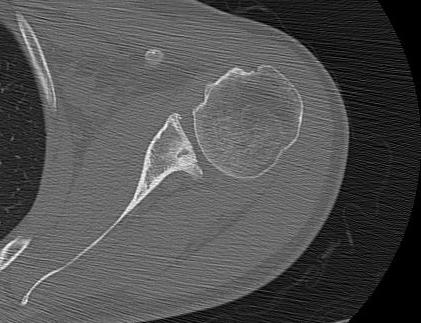

CT

Hill Sachs lesion / posterior bony bankart / glenoid retroversion

Reverse Hill Sachs / Posterior bony Bankart / Glenoid retroversion